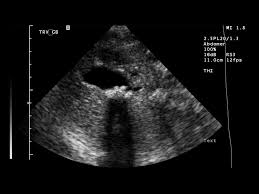

-Confirmation of the diagnosis of cholecystitis requires demonstration of the gallbladder wall thickening or edema on an imaging study (usually ultrasound)

-the study of choice for diagnosis is ultrasound. CT scan of the abdomen is less sensitive